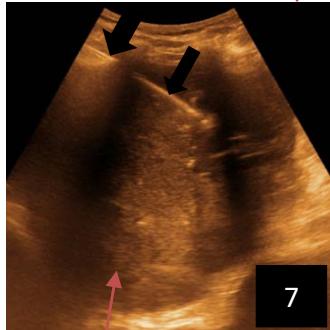

Iconography 1: 54-year-old patient with an intra-splenicsolid mass, anatomopathologically compatible with lymphoma: images 1 and 2: right pleurisy of moderateabundance, image3: celiacadenopathy, image 4: free ascites of moderateabundance, images 5 and 6: intra-splenicsolid mass of around $1418.16\mathrm{ml}$ in B mode and elastographyshowing areas of tumourrigidity, images 7-10: oblique linear images, showingbiopsy gun tracks.